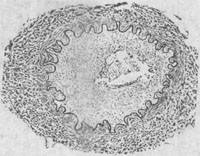

图18-24 弥漫性肺出血型钩端螺旋体病的肺切面几乎全部呈出血变实,酷似血凝块 2.肝 肝的病变以黄疸出血型患者最为显著。肉眼观察肝肿大,质软,色黄。镜下见肝细胞混浊肿胀、脂肪变性和小叶中央灶性坏死。Disse腔水肿,肝细胞索离解。枯否细胞增生。汇管区胆小管可见胆汁淤滞和淋巴细胞、中性粒细胞及少量嗜酸性粒细胞浸润。钩体含量在全身各器官、组织中,以肝为最多。主要存在于Disse腔和毛细胆管内,肝细胞和枯否细胞内可见变性的钩端螺旋体。由于肝细胞的损害可引起胆汁排泄功能降低和凝血功能障碍,故临床上可见重度黄疸和广泛皮肤、粘膜出血。严重者可发生急性肝功能不全或肝肾综合征。 3.肾 肾损害可以单独存在(肾型钩端螺旋体病),也可与流感伤寒型、肺出血型,特别是黄疸出血型同时存在。肉眼观,肾稍肿大,切面见皮质苍白,髓质淤血,偶见肾包膜出血。镜下主要见间质性肾炎和肾小管上皮细胞不同程度的变性坏死。肾小管腔扩大,其中含有蛋白、红细胞、粒细胞和细胞碎片,并可形成管型阻塞肾小管管腔。肾间质可见充血、水肿或出血,有散在的小灶性炎细胞浸润,主要为淋巴细胞、单核细胞、少量中性和嗜酸性粒细胞浸润。肾小球一般无明显改变。肾组织内易查见钩端螺旋体,可见于肾间质、肾小管上皮细胞及肾小管腔内。肾损害严重者可引起急性肾功能不全,造成肾损害的原因除毒素作用外,肾微循环障碍所致的缺氧亦起一定的作用。 4.其他器官组织病变 (1)心脏:心脏常扩大,质地较软,心外膜和心内膜可见出血点。镜下见心肌细胞普遍混浊肿胀,偶见灶性坏死。间质有水肿、出血和血管周围炎,以单核细胞浸润为主,夹杂有少数中性粒细胞和淋巴细胞。临床上可出现心动过速、心律紊乱及心肌炎的征象。 (2)横纹肌:以腓肠肌病变最为明显。镜下主要见肌纤维节段性变性、肿胀、横纹模糊或消失,并可出现肌浆空泡或溶解性坏死,肌浆及肌原纤维溶解消失,仅存肌纤维轮廓。间质有水肿、出血和少量炎细胞浸润。临床上出现腓肠肌压痛。 (3)神经系统:部分病例有脑膜及脑充血、出血、炎细胞浸润和神经细胞变性。这些病变在钩体病的脑膜脑炎型最为明显。临床上出现脑膜脑炎的症状和体征。 (4)脾、淋巴结:单核巨噬细胞增生和炎细胞浸润,可引起脾和淋巴结肿大。 (5)肾上腺:皮质内脂质减少或消失,皮质和髓质均可有出血及灶性或弥漫性炎细胞浸润。 【后发症】 1.眼部病变 眼部病变多在热退后1周至1月左右发生。最常见者为虹膜睫状体炎、脉络膜炎或全葡萄膜炎。并可出现巩膜表层炎,球后神经炎或玻璃体混浊。 2.脑动脉炎 患者多为儿童,亦可为青壮年。患者常在急性期症状消失后1~5月出现偏瘫和失语等症状。主要病变是脑底多发性动脉炎及其所引起的脑实质损害。病变主要累及脑底动脉各干支,以大脑中动脉及大脑前动脉病变最重,大脑后动脉次之。病变呈跳跃性节段性分布,使该动脉粗细不匀、僵直或呈灰白色绳索状。此外,在基底节及其邻近脑实质内可见毛细血管及小静脉明显扩张充血,有的聚集成簇。镜下见受累动脉早期可为全动脉炎,较晚期则主要为增生性动脉内膜炎,使内膜显著增厚,可引起血管腔狭窄甚至闭塞,偶尔可并发血栓形成(图18-25)。脑实质可因缺血而发生轻重不一和不同部位的水肿、出血和多发性软化灶。

图18-25 钩端螺旋体病后发症——脑动脉炎模式图动脉内膜高度增生变厚,管腔变狭窄